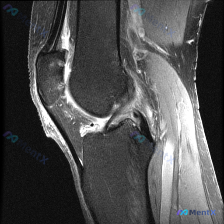

今天整理了一张膝关节MRI的读片分析,这个病例的思路很有代表性,分享给大家。 病例影像基础信息 这是一张膝关节MRI矢状位T1加权像,图像质量良好,对比度清晰,无明显伪影,层面可显示股骨髁、胫骨平台、交叉韧带等核心结构。 系统读片结果 1. 骨与软骨整体情况:股骨远端、胫骨近端骨髓信号均匀,无局灶低...

刚整理了一份有意思的膝关节MRI读片病例,临床提示观察到软骨异常,但单张T1加权矢状位影像却没看到明确异常,把分析思路整理出来和大家讨论。 一、病例基本影像信息 这是一张膝关节T1加权矢状位旁矢状位MRI图像,显示区域包括股骨远端、胫骨近端、髌骨、髌腱、Hoffa's脂肪垫和部分后交叉韧带,主要观察...